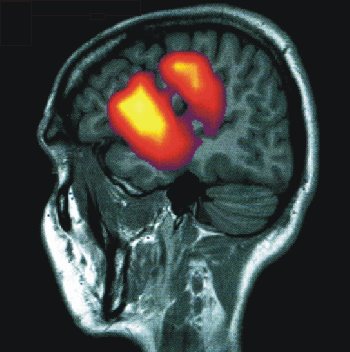

Durch graphische Kombination von morphologischen und funktionellen Daten können wichtige Zusammenhänge veranschaulicht werden. Hier ist diese Kombination anhandt von Messungen der Hirnaktivität dargestellt.

Das Bild rechts zeigt die Überlagerung eines Kerspintomogramms (grau) und einer Messung der durch Hirnströme verursachten Magnetfelder (Magnetenzephalographie). Mit dieser Methode kann die Aktivität in spezifischen Arealen des Gehirns definierten Tätigkeiten zugeordnet werden. Die räumliche Auflösung ist bei der Magnetenzephalographie ca 5 mm, und die Methode bietet eine sehr hohe zeitliche Auflösung, so daß auch schnelle, insbesondere rhythmische Aktivitätsmuster von Neuronen erfasst werden können.

Aus: Forschen in Jülich, 1/2000, Forschungszentrum Jülich

Sowohl im linken als auch im rechten Bild werden sehr unterschiedliche Arten von Daten miteinander kombiniert. Das NMR- Bild ist eine Art Photo einer einzelnen Gehirnebene - im allgemeinen die Darstellung einer typischen Hirnstruktur. Die funktionellen Messungen hingegen sind Resultate komplizierter Datenverarbeitung. Messungen vieler Einzelbilder werden gemittelt, gelegentlich auch Bilder, die von mehreren Menschen stammen. Messungen vor und nach einem Stimulus werden voneinander subtrahiert, so daß Differenzbilder entstehen. Diese gemittelten Differenzbilder werden einer genauen statistischen Analyse unterworfen: Wo sind statistisch signifikante Unterschiede zwischen der Kontrollmessung und der Messung während des Stimulus auszumachen? Die Signale sind oft äußerst schwach und müssen mit erheblichem Rechenaufwand gesucht werden. Zur graphischen Verdeutlichung dient die Falschfarbendarstellung, mit der auch die kleinste Änderung als blau-zu-rot-Signal dargestellt werden kann.